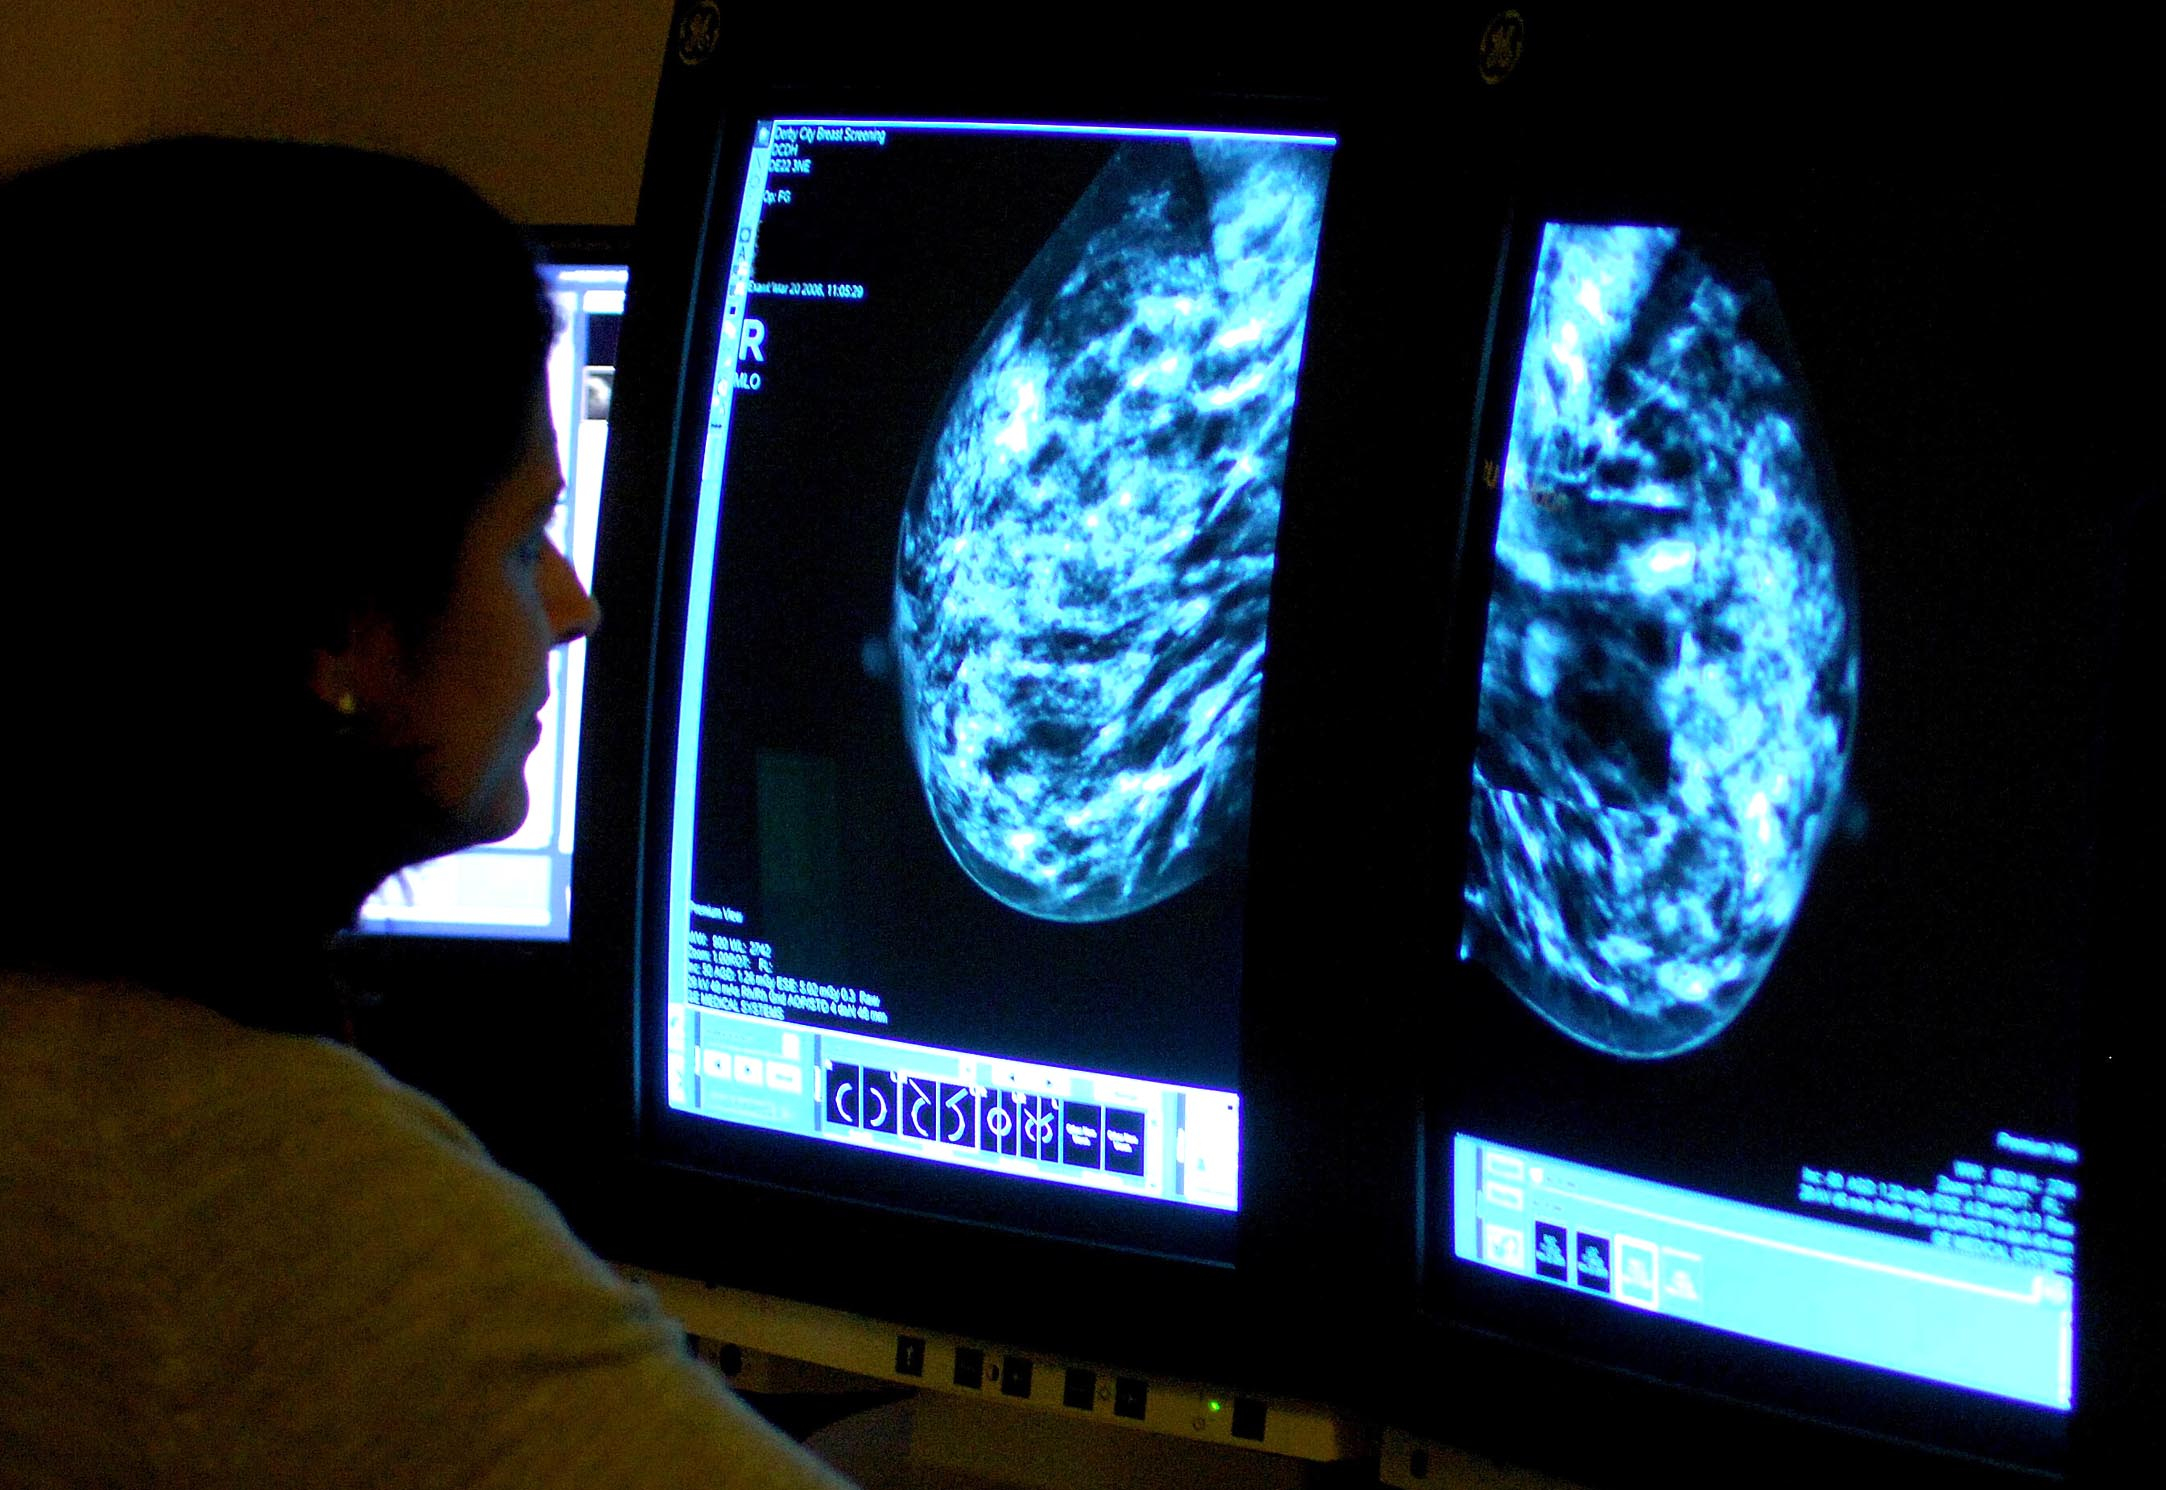

More women in Devon undergo breast cancer screening – as NHS England target met for first in five years

Breast screening uptake in Devon remains below pre-pandemic levels